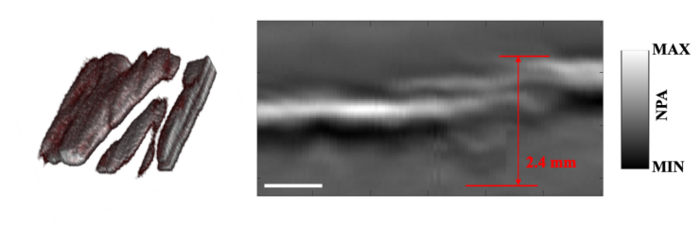

The research team developed a high-power all-fiber hybrid optical parametrically-oscillating emitter (HOPE) at 1930 nm. It is the best wavelength for determining the water content of tissue and fats. The HOPE emits laser pulses every 15 nanoseconds (ns), with a 1 nm bandwidth. The research team verified the performance of their system through a proof-of-concept optical-resolution PA microscope system.

The team found that the 1930 nm system improved penetration depth by 2.4 mm. The research team owed it to reducing photon scattering in the tissue within the shorter wavelength near-infrared lasers. The improved penetration ability could facilitate measurable imaging of water content in the deep tissue.